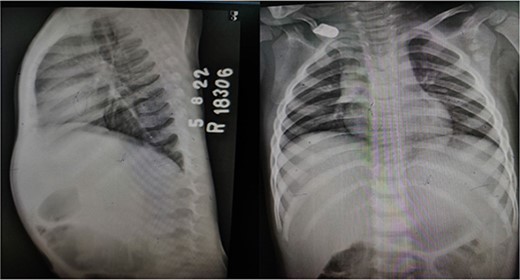

X-ray chest and dorsal spine seemed within normal limits (Fig. 2). Ultrasonography (USG) of the mass revealed an anechoic 1.8 × 1.2 cm lesion with no internal vascularity or calcification (Fig. 3). It was found to be in the subcutaneous plane with a minor extension to the muscular plane over the mid-upper back region, giving it an impression of a nerve sheath tumor. The hemogram was within normal limits. At this stage, we had a differential diagnosis of a nerve sheath tumor in mind.

X-ray dorsal spine anteroposterior and lateral views, showing no significant abnormality.